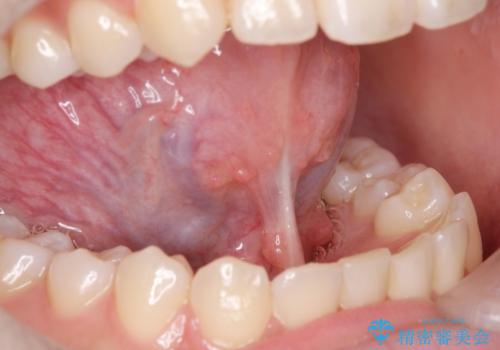

[ 舌小帯の形成 ] 滑舌を改善したい

担当医 大元洋佑

![[ 舌小帯の形成 ] 滑舌を改善したいの症例 治療前](https://seimitsushinbi.jp/wp/wp-content/uploads/2022/10/fa797540f242dace21c05a8161580df4-500x350.jpg?v=1665555891)

![[ 舌小帯の形成 ] 滑舌を改善したいの症例 治療後](https://seimitsushinbi.jp/wp/wp-content/uploads/2022/10/45c8c51b664db205e71949fb1e2ec432-500x350.jpg?v=1665555859)